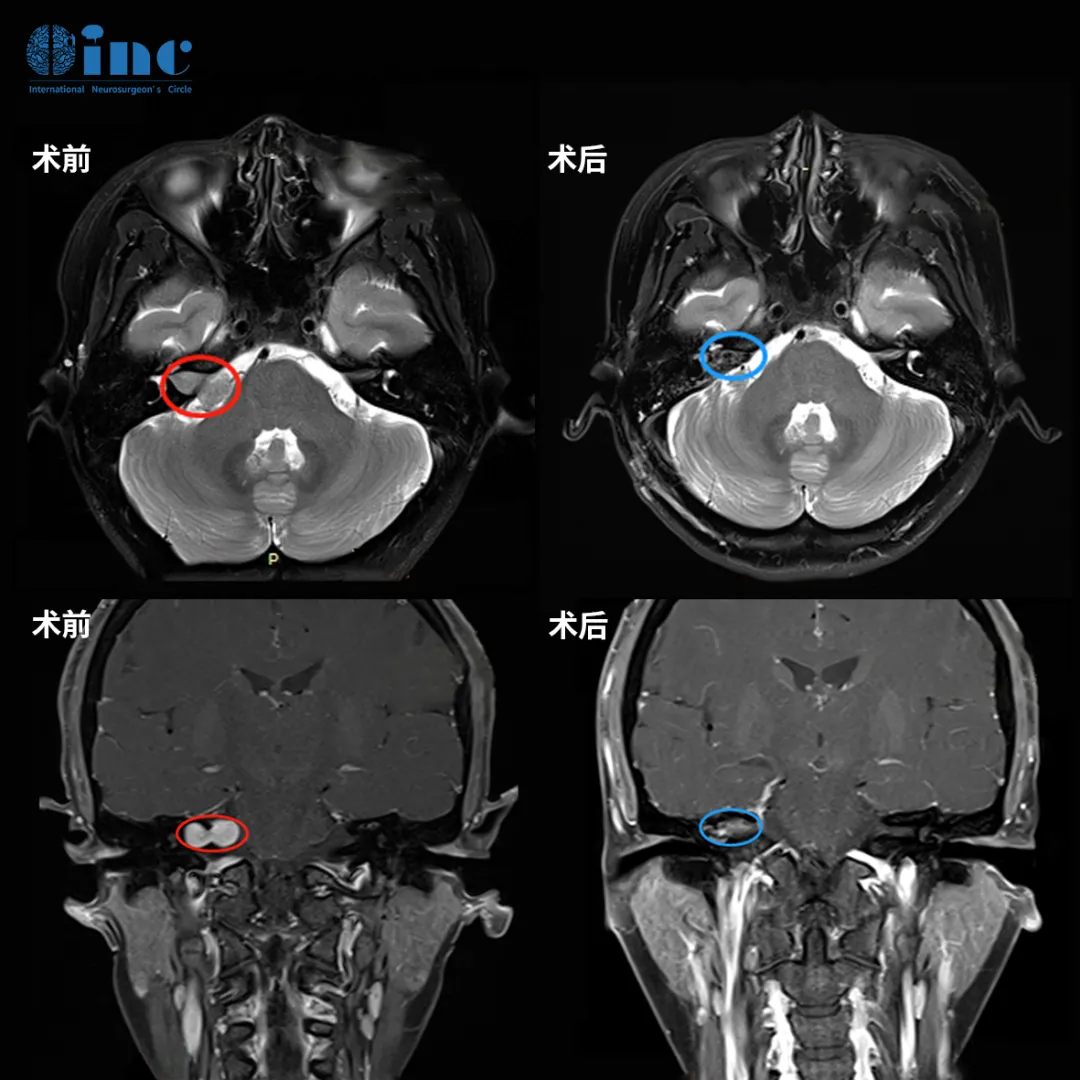

因此,她找到INC巴教授主刀手术,结果令人欣慰:肿瘤不仅被完全切除,面神经也成功保留,未发生面瘫。